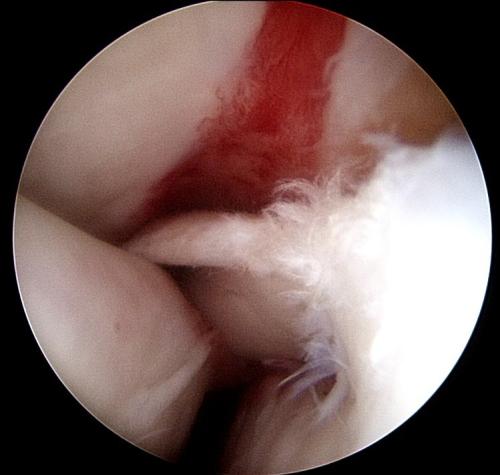

A rehabilitation program will be provided for your horse. This may also include suggestions for post-surgical treatments. For example, it is routine to perform Hyaluronic acid/corticosteroid injections at 2 weeks post surgery following arthroscopic chip/fragment removal. When there is substantial soft-tissue or cartilage injury, we often recommend biologic therapies.